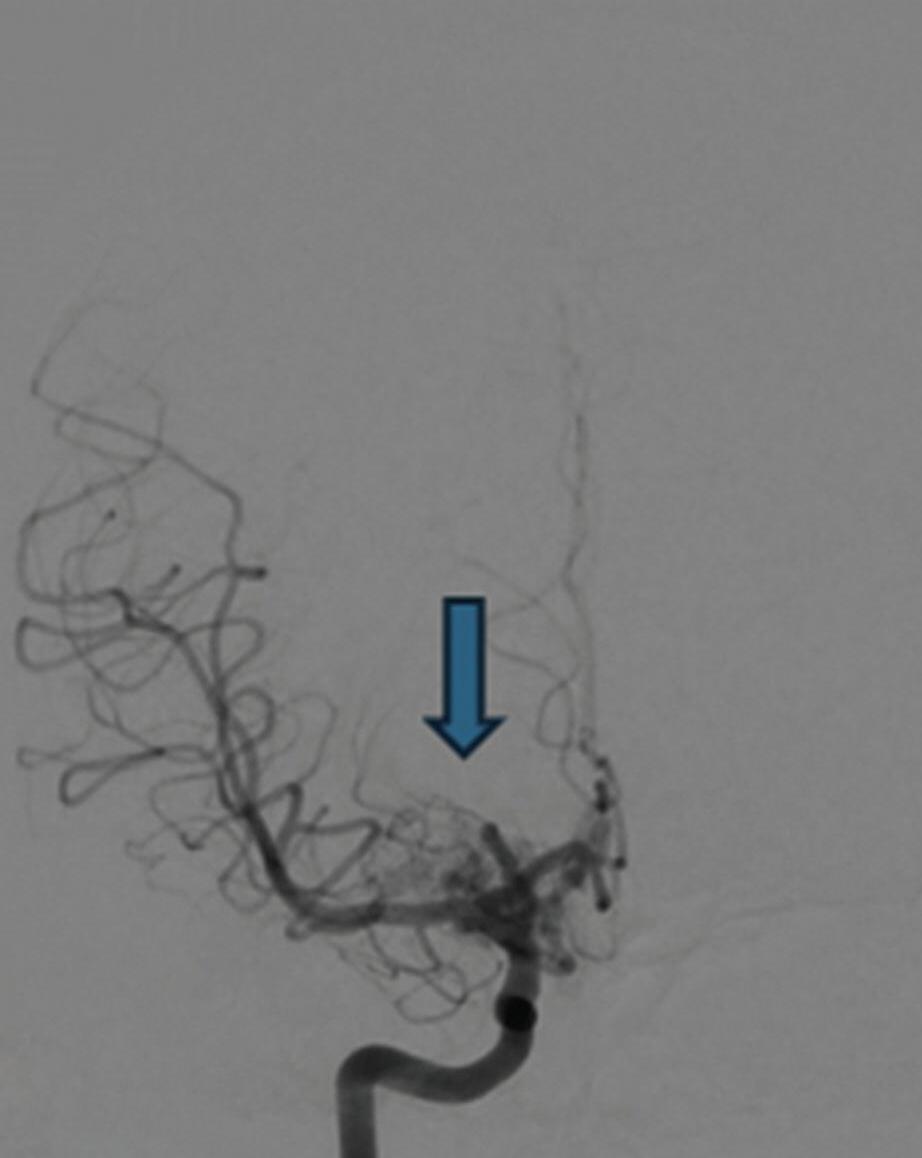

Fig. 1-8. (a-c) RNM T1 com contraste, cortes sagital (a), coronal (b) e axial (c) demonstrando MAV não rota com nidus localizado no lobo occipital à esquerda (setas longas). (d) Arteriografia digital cerebral com injeção de contraste via carótida direita (AP) mostrando a contribuição da carótida direita na irrigação da MAV contralateral. (e,f) Com injeção de contraste via carótida esquerda, em Perfil e AP respectivamente, observa-se nidus compacto nutrido por ramos da artéria cerebral média à esquerda e a veia de drenagem precoce se dirigindo para o seio sagital superior. Projeções em AP (g) e em perfil (h) demonstrando a contribuição do sistema vertebrobasilar por meio de ramos distais da artéria cerebral posterior à esquerda e drenagem para os seios sagital superior e sigmoide à esquerda (setas curtas).

Fig. 1-9. RNM T2 em cortes (a) axial e (b) sagital. (c,d) Tractografia axial – sagital, demonstrando a posição de uma MAV não rota localizada na superfície basal do lobo frontal, nos giros orbitários e reto à direita (setas longas). Arteriografia digital cerebral com injeção de contraste via carótida direita, (e) AP e (f) em perfil demonstrando MAV nutrida por ramos da artéria cerebral média e cerebral anterior direita e drenagem para o seio sagital superior (seta curta).